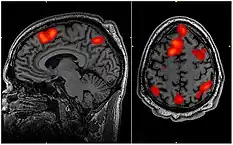

This specific FMRI scan determined which areas of the brain are activated during working memory tasks, but this type of imaging could also determine the areas of brain activated during flow experiences

The neuroscientific underpinnings of flow are a developing field with significant potential. With advancements in neuroimaging technologies, as highlighted by Linden (2021), the opportunity to correlate psychological experiences of flow with their physiological counterparts becomes increasingly feasible [113]